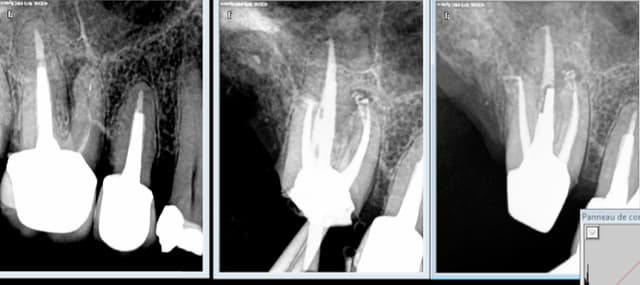

Ils viennent TOUS avec des signes d'appels. Douleur ou dent pétée ou les 2. Tiens encore un. -)

Tu sors toujours l'artillerie lourde. Et c'est justifié. -)

Capture d e cran 2016 02 04 12.21 - Eugenol